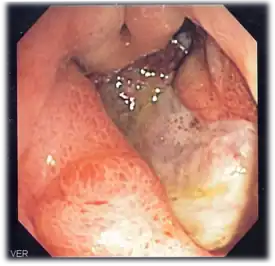

- Endoscopy, to check for stomach lining inflammation and mucous erosion